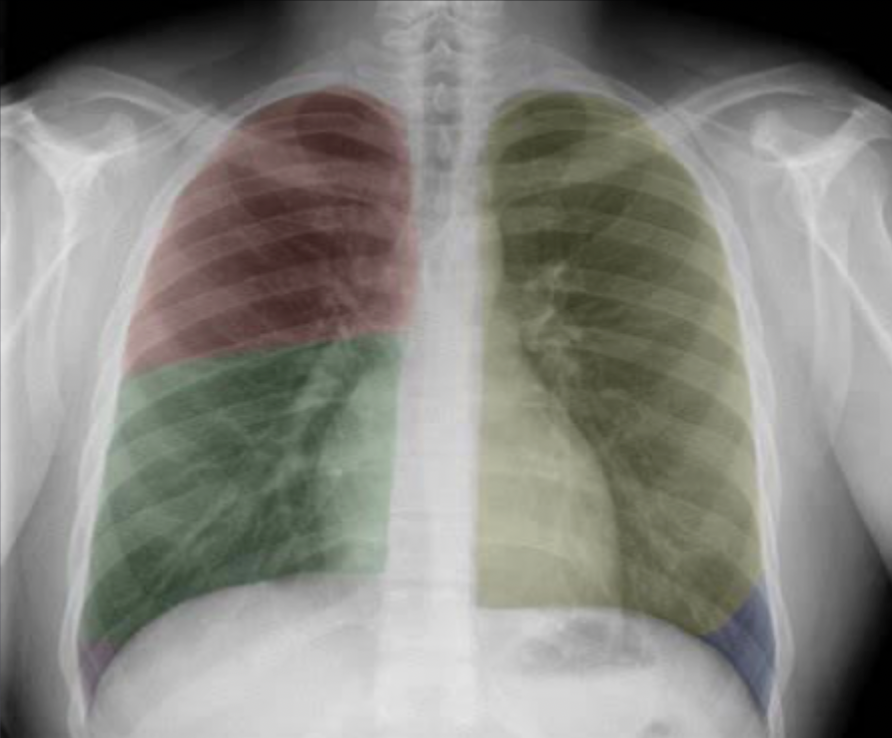

Which lobe is which ?

How well did you know this?

The lingular segments of the left upper lobe abut the left heart border, so can be thought of as anatomically equivalent to the middle lobe in the right lung.

“Abut” means: to lie next to or to directly touch.